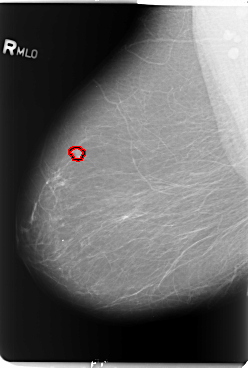

B_3102_1.RIGHT_MLO

FILE: B_3102_1.RIGHT_MLO.OVERLAY

TOTAL_ABNORMALITIES 1

ABNORMALITY 1

LESION_TYPE MASS SHAPE LOBULATED MARGINS CIRCUMSCRIBED-ILL_DEFINED

ASSESSMENT 4

SUBTLETY 5

PATHOLOGY BENIGN

TOTAL_OUTLINES 1

BOUNDARY